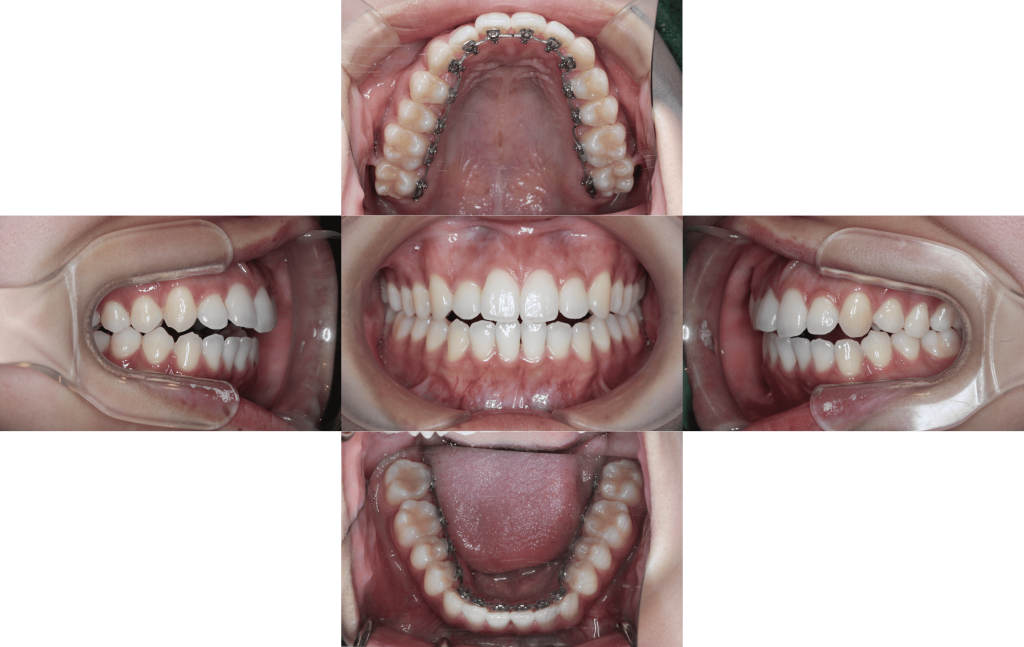

After

約2年経過

治療費用

¥1,375,000

治療期間

約2年(最終微調整はマウスピース矯正に移行する予定です。)

抜歯

非抜歯

マルチブラケット装置(裏側矯正)

副作用、リスク

歯肉退縮,歯根吸収,疼痛,咬合の違和感,装置の違和感,虫歯,歯肉炎